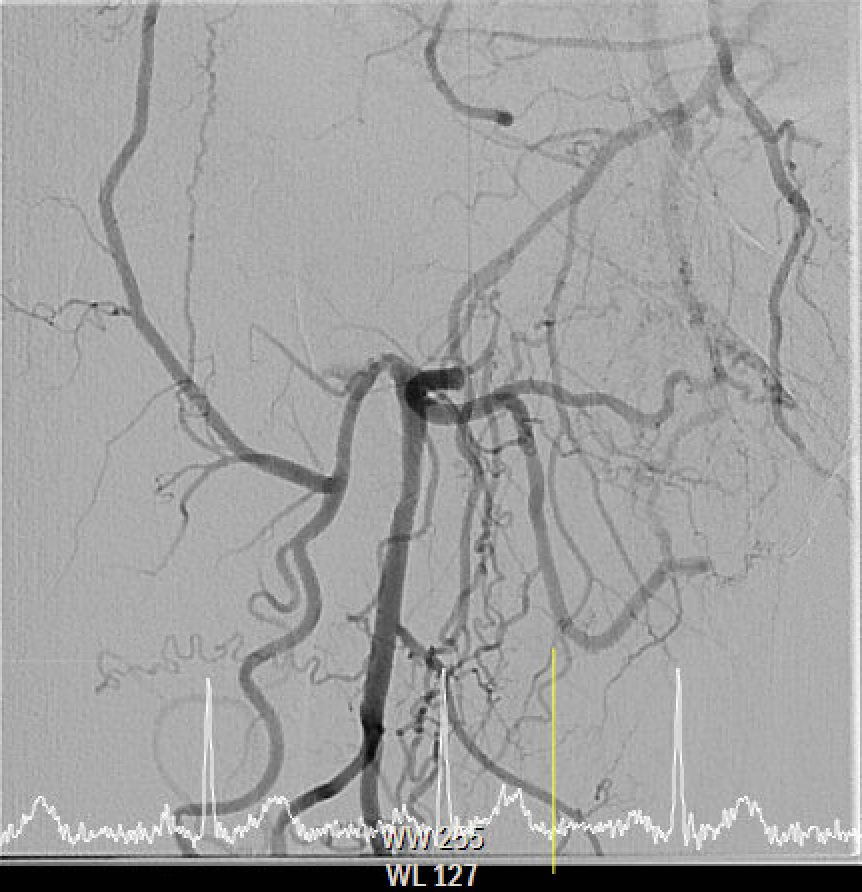

The angiography confirmed extensive Chronic Total Occlusion (CTO) of the right External Iliac Artery (EIA), Common Femoral Artery (CFA), and proximal Superficial Femoral Artery (SFA). The limb's circulation was critically dependent on collateral flow: the Deep Femoral Artery (DFA) was patent and supplying the distal SFA. Distally, a 50% stenosis was noted in the Popliteal Artery, but the Below-the-Knee (BTK) arteries were patent.

The procedure utilized a hybrid retrograde and antegrade approach. Retrograde access was established via a micropuncture kit under angiography guidance into the distal Superficial Femoral Artery (dSFA), but wiring attempts failed due to an intervening aneurysm, necessitating a switch to the antegrade route from the left brachial artery. A wire escalation technique, assisted by a microcatheter, successfully crossed the extensive CTO, and was met with retrograde microcatheter and externalized via the dSFA puncture site (retrograde access), establishing through-and-through wire access. Following initial balloon predilation and IVUS confirmation of diffuse thrombus, extensive angioplasty was performed. Definitive treatment involved deploying multiple overlapping GORE¢ç VIABAHN¢ç Endoprosthesis diameters (from 6mm to 8mm) from the dSFA proximally to the pEIA via left femoral access, effectively treating the long occlusion and excluding the aneurysm. A COOK Zilver Flex iliac stent reinforced the proximal landing zone. The stented segment was rigorously post-dilated up to 12 atm. The procedure concluded with a Drug-Eluting Balloon (DEB) PTA (BOSTON Ranger Paclitaxel-Coated PTA Balloon Catheter) to the dSFA to mitigate restenosis in the non-stented region. Final angiography confirmed good flow without distal embolization.